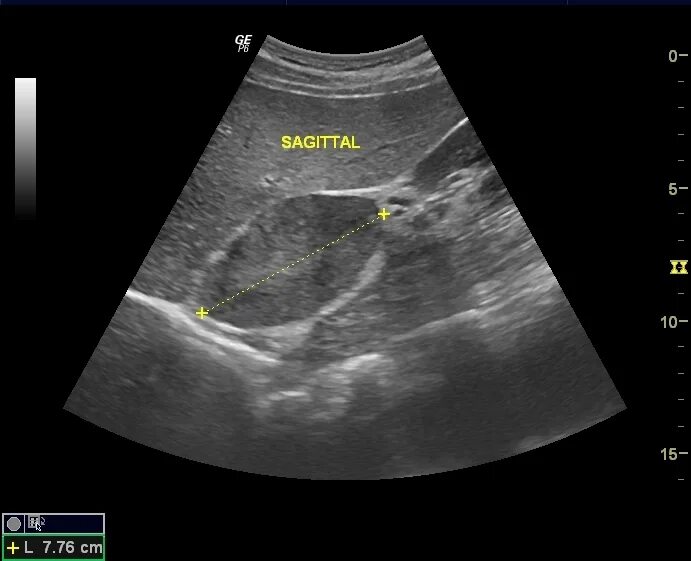

Узи сердца узи почек